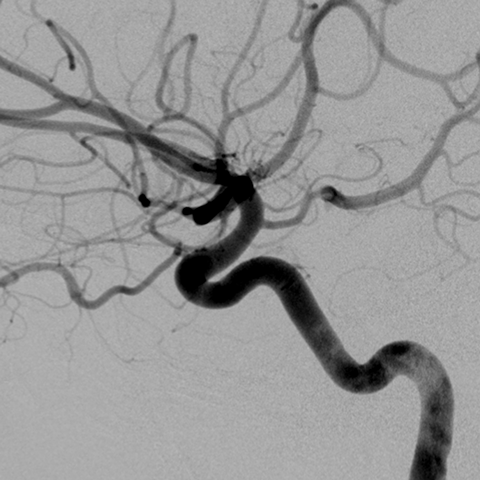

Circle of Willis (normal anatomy) [6 of 6]